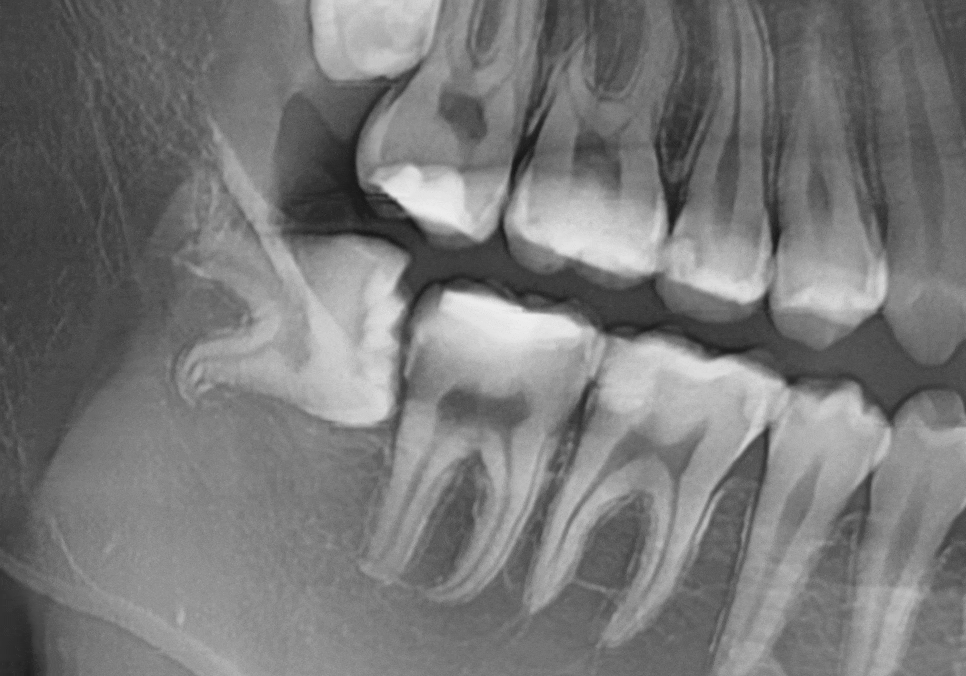

얼마 전 한 환자분께서

오른쪽 아래 어금니 쪽에

음식물이 자꾸 끼고

욱신거린다는 증상으로 오셨습니다.

입안을 겉에서만 보았을 때는

사랑니(#48)가 머리만 살짝 보이고 있어서

큰 문제가 없어 보였죠.

하지만 엑스레이를 찍어보니

상황이 조금 달랐습니다.

사랑니가 앞 치아(#47) 쪽으로

비스듬히 누워 있는 상태였거든요.

만약 사랑니를 1~2년만 더 일찍 뽑았더라면,

아마 신경을 제거하고 전체를 씌우는

큰 치료까지는 가지 않았을 테니까요.

221231(전) 240228 (후)